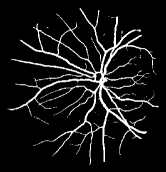

Refer to caption

Figure 2: An overview of the proposed BTS-DSN. Four uppermost cuboids represent four groups of convolutions of VGGNet. If ResNet-101 is used as backbone, then four uppermost cuboids are conv1, res2, res3 and res4.